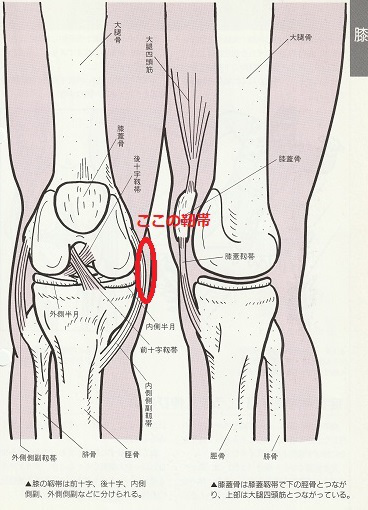

膝窩筋の機能と膝の痛みについて 名古屋の鍼灸接骨院 ハートメディカルグループ

膝関節痛の理学療法 半月板由来の疼痛に対する評価とアプローチ 理学療法士による理学療法士のためのnote Note